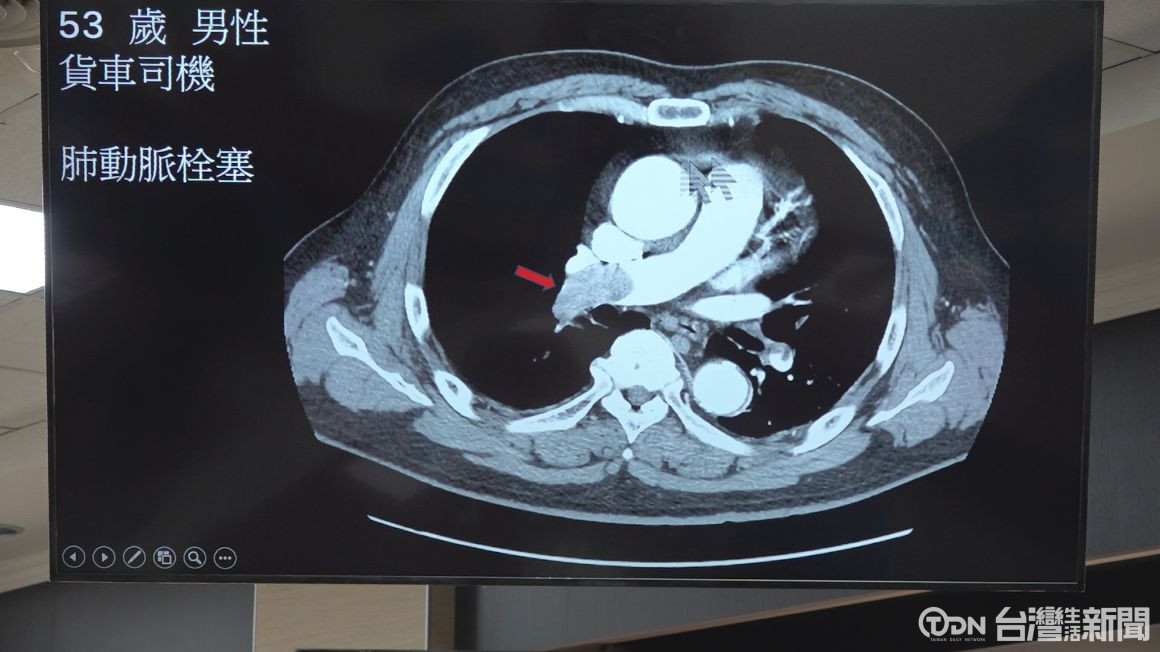

日前臺南市立醫院接獲,一名有高血壓病史的53歲貨車司機,因突然出現嚴重呼吸困難、感覺「喘不過氣」緊急前往急診就醫,經由臺南市立醫院心臟內科胸部電腦斷層檢查確診為肺動脈栓塞,隨即收治加護病房治療,醫療團隊每日施打兩劑抗凝血劑,持續治療五天後,患者呼吸逐漸穩定,順利脫離危險期。

▲肺動脈栓塞。/記者 陳嘉升攝